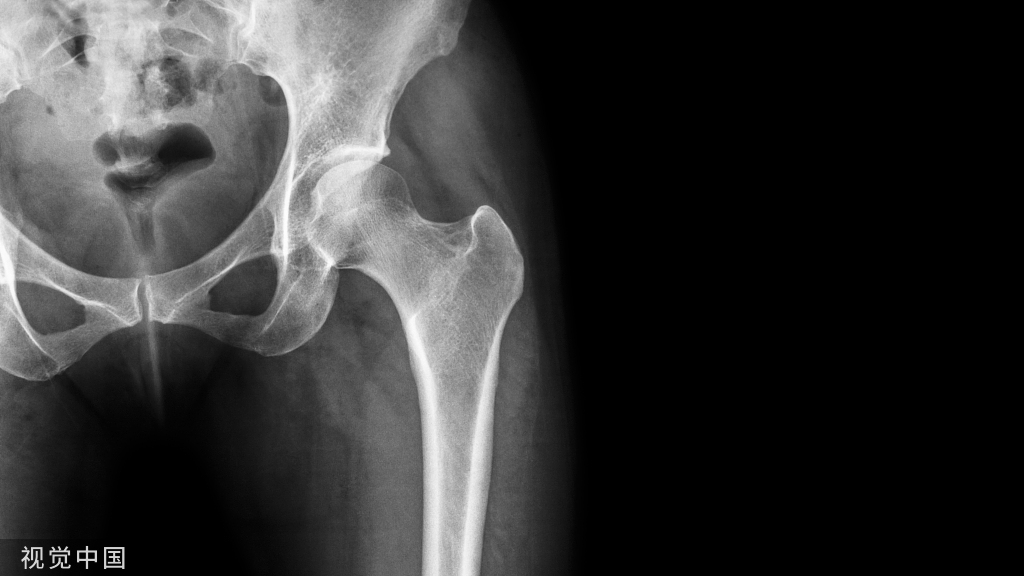

几十年来,稳定的中性下肢力线是全膝关节置换术(TKA)的首要原则,因为其可获得长期的临床疗效和假体生存率。

机械对线技术【Mechanical Alignment (MA) technique】 MA技术,即股骨远端和胫骨近端截骨面均垂直机械轴线,使下肢轴线与关节线垂直。